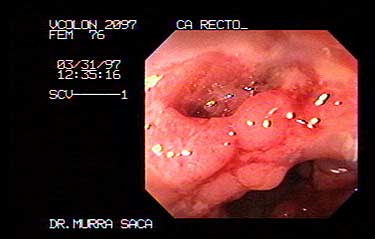

Paciente femenina de 76 Años quien presenta enterorragia, Adenocarcinoma del recto